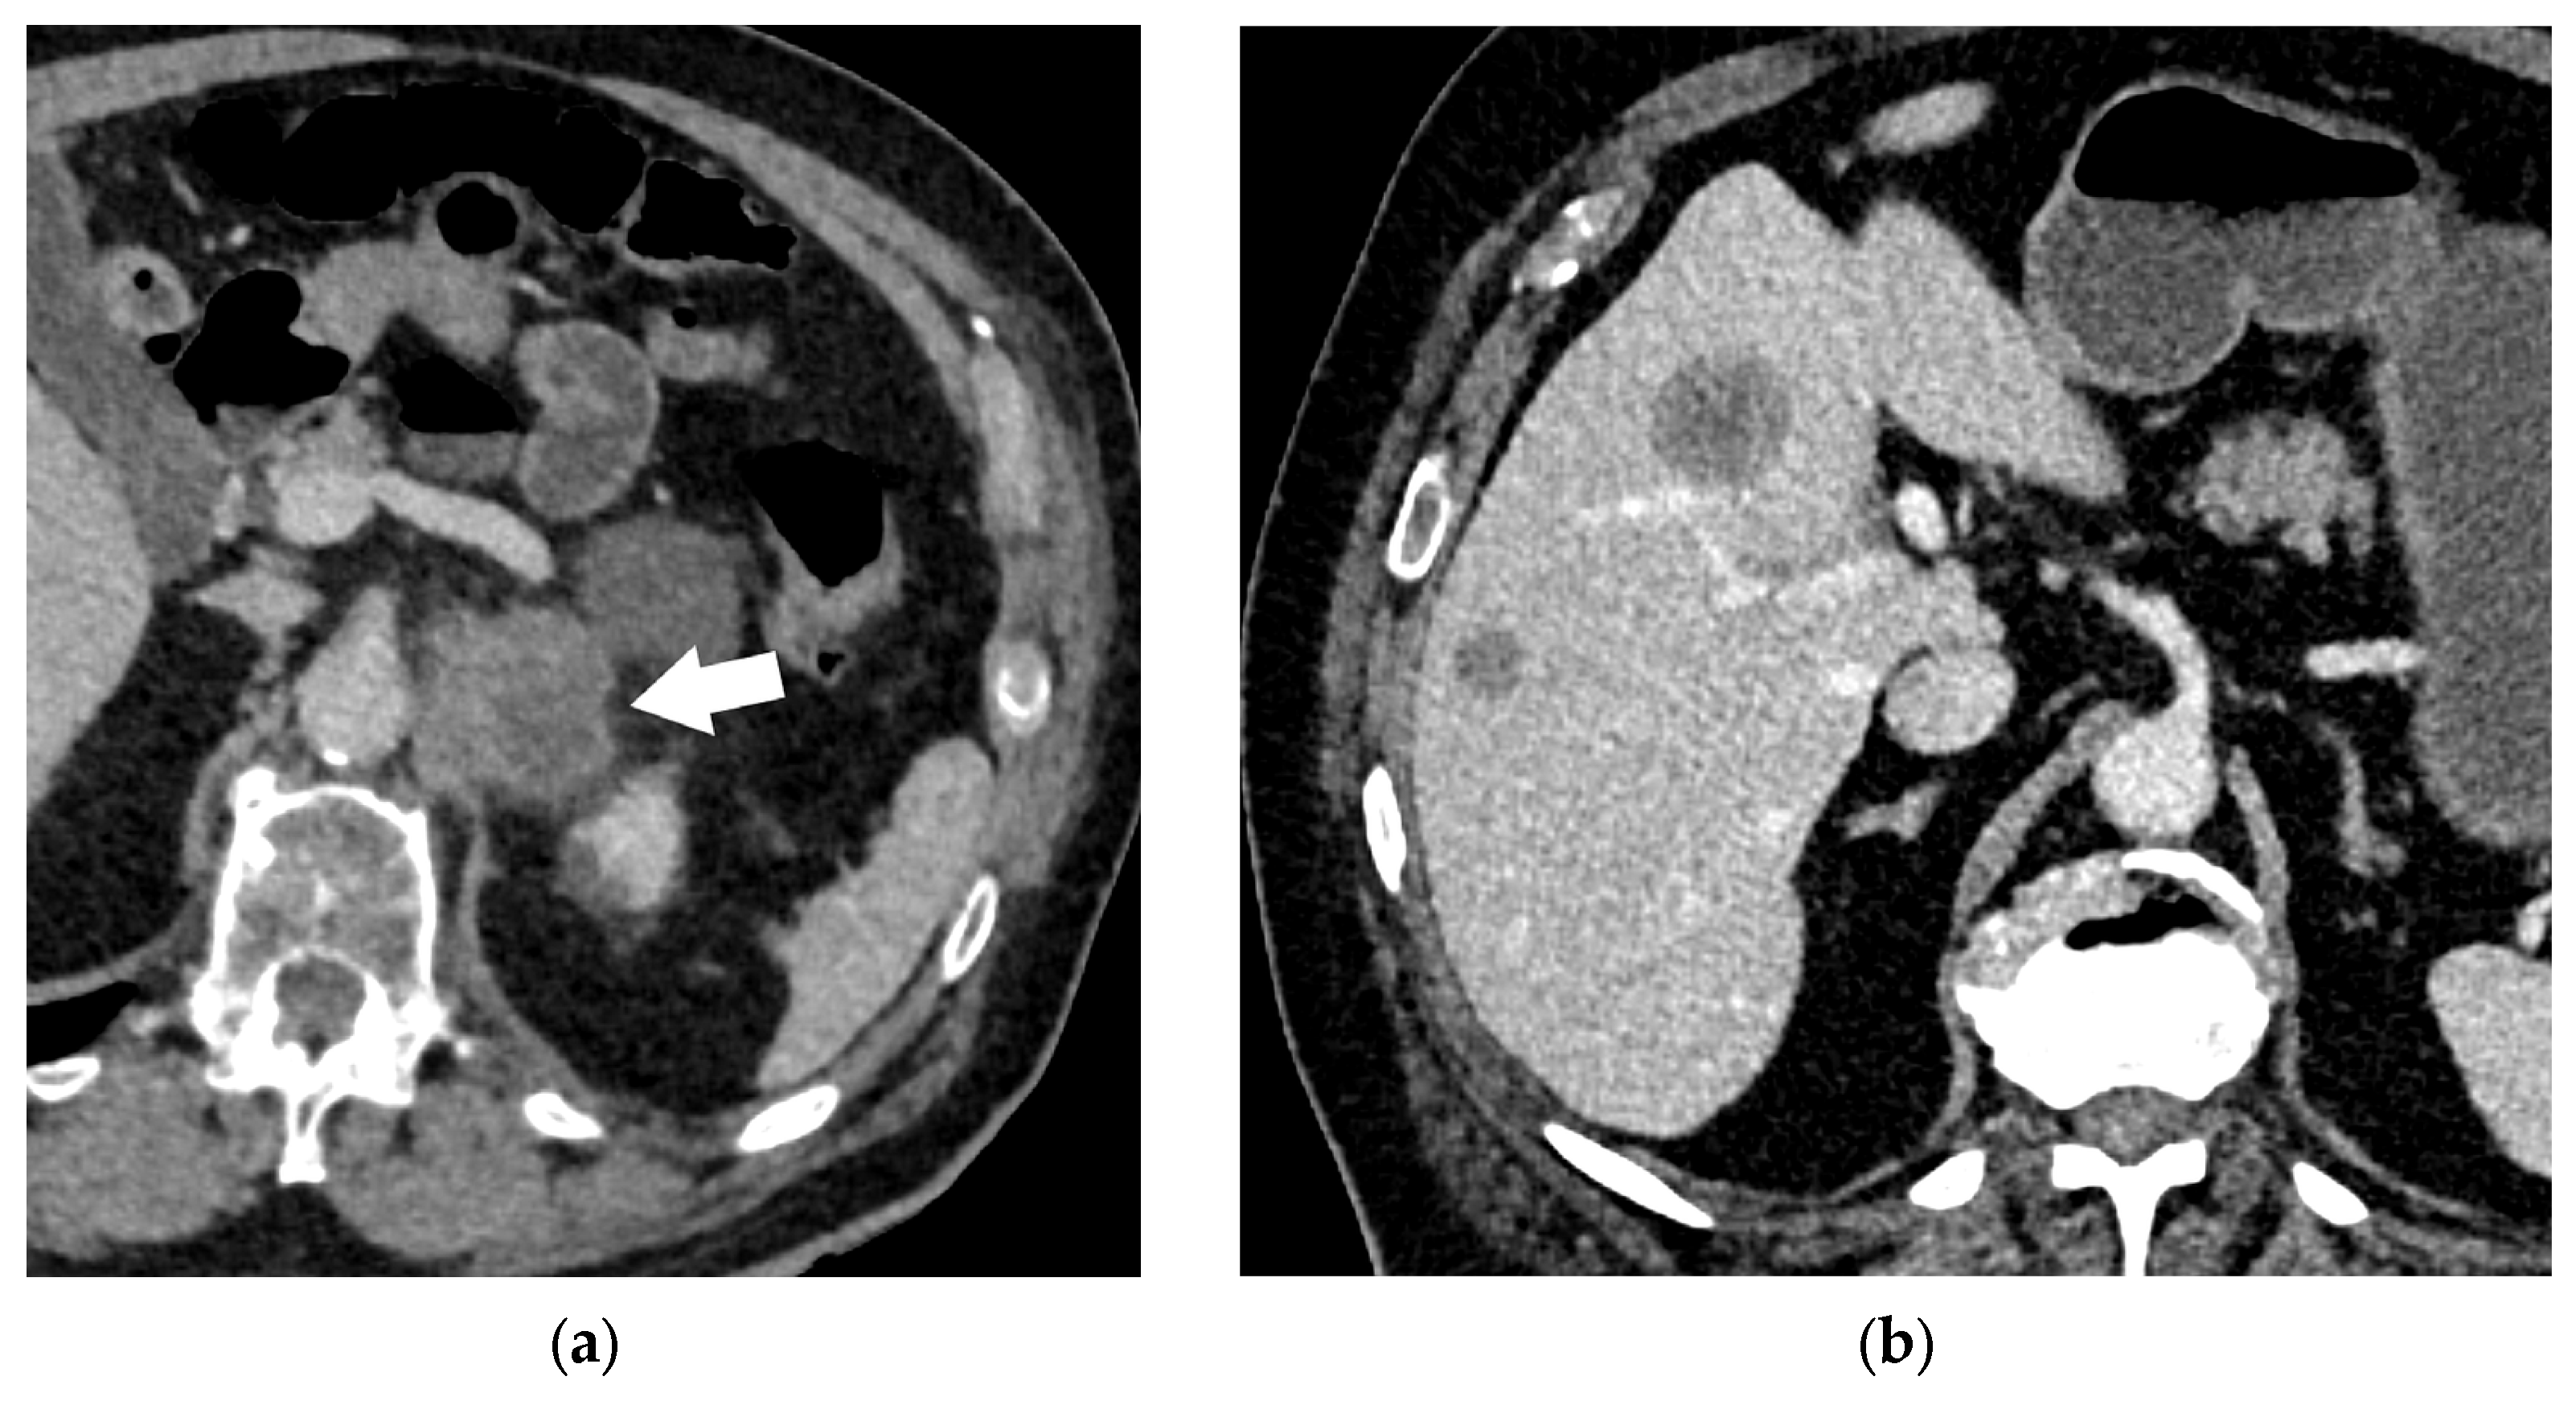

- Gore, R.M.; Thakrar, K.H.; Wenzke, D.R.; Newmark, G.M.; Mehta, U.K.; Berlin, J.W. That liver lesion on MDCT in the oncology patient: Is it important? Cancer Imaging 2012, 12, 373–384. [Google Scholar] [CrossRef]

- Gulpinar, B.; Peker, E.; Kul, M.; Elhan, A.H.; Haliloglu, N. Liver metastases of neuroendocrine tumors: Is it possible to diagnose different histologic subtypes depending on multiphasic CT features? Abdom. Radiol. 2019, 44, 2147–2155. [Google Scholar] [CrossRef]

- Maino, C.; Vernuccio, F.; Cannella, R.; Cortese, F.; Franco, P.N.; Gaetani, C.; Giannini, V.; Inchingolo, R.; Ippolito, D.; Defeudis, A.; et al. Liver metastases: The role of magnetic resonance imaging. World J. Gastroenterol. 2023, 29, 5180–5197. [Google Scholar] [CrossRef]

- Ozaki, K.; Higuchi, S.; Kimura, H.; Gabata, T. Liver Metastases: Correlation between Imaging Features and Pathomolecular Environments. Radiographics 2022, 42, 1994–2013. [Google Scholar] [CrossRef]